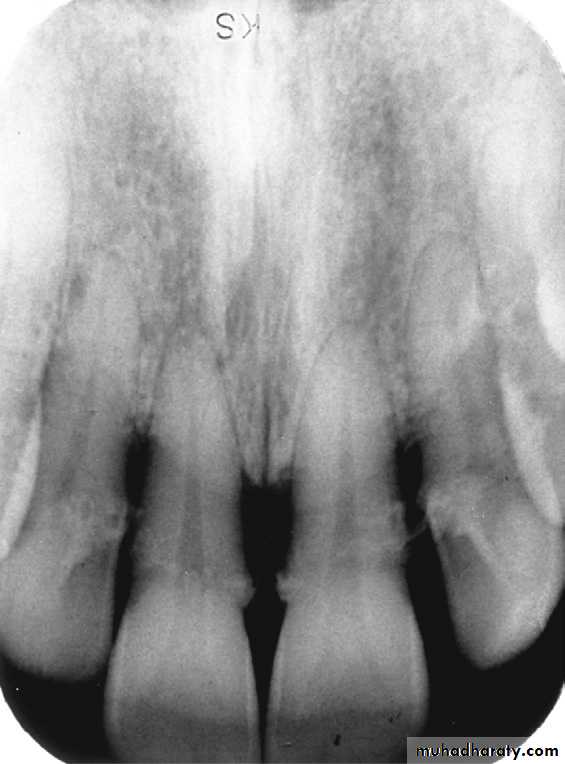

Alveolar crest: The normal healthy alveolar crest is located approximately 1.5 to 2.0 mm apical to the cementoenamel junctions (CEJs) of adjacent teeth.The shape and density of the alveolar crest vary between the anterior and posterior regions of the mouth. In the anterior regions, the alveolar crest appears pointed and sharp and is normally very radiopaque .In the posterior regions, the alveolar crest appears flat, smooth, and parallel to a line adjacent CEJs .The alveolar crest in the posterior regions appears slightly less radiopaque than that in the anterior regions

Healthy alveolar crest in the anterior region that appears pointed and highly radiopaque

Periodontal ligament space: The normal periodontal ligament space appears as a thin radiolucent line between the root of the tooth and the lamina dura. In health, the periodontal ligament space is continuous around the root structure and is of uniform thicknessHealthy alveolar crest, normal lamina dura, and periodontal ligament space on a periapical image.